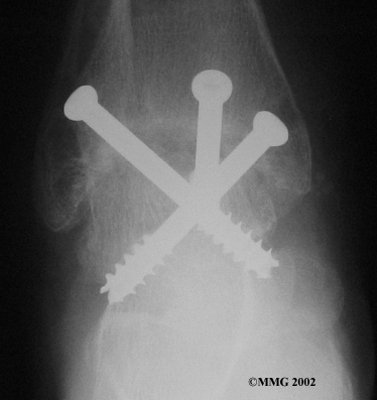

It is important when the surfaces are removed that the angles of the cut surfaces are correct. When the tibia is brought against the talus, the foot should be at a right angle to the lower leg. Once the cuts are made the bones must be held in place while they fuse. This can be done using large metal screws and metal plates if necessary. The screws are usually under the skin and are not removed unless they begin to rub and cause pain.

Inserting the screws

After ankle fusion, the physical therapists at Fyzical Bolingbrook can help you learn to walk smoothly and without a limp. Although time needed for recovery varies among patients, an ankle brace will typically replace your cast after eight to 12 weeks. Your surgeon will take X-rays frequently to see if the bones are fusing together. You will probably need to use crutches during the time you wear the cast. As the fusion grows stronger, you will begin to put more weight on your foot when walking.